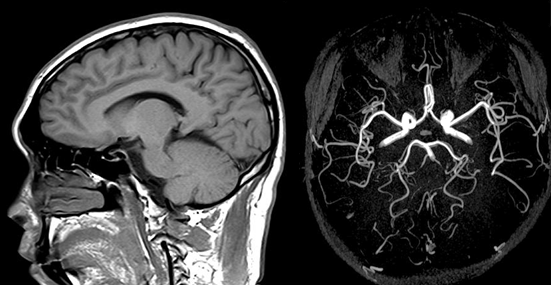

脳ドック(脳MRI+MRA)

脳ドックは脳卒中・脳腫瘍などを無症状の早期のうちから発見し、予防に繋がる検査です。症状のない軽微な脳梗塞(無症候性脳梗塞)もリスク評価に重要です。MRA(血管撮影)により動脈瘤や血管狭窄・動脈硬化のチェックもできます。40歳以上で脳卒中の家族歴のある方や生活習慣病リスクのある方、喫煙歴や大酒家の方にお勧めしています。

脳・頸動脈MRIドック(脳MRI+MRA+頸動脈MRA)

脳ドックによる脳卒中や脳腫瘍の検索に加えて、頸部MRA(血管撮影)で狭くなった頸動脈や瘤をチェックできます。生活習慣病リスクのある方にお勧めしています。

脳・頸動脈超音波ドック(脳MRI+MRA+頸動脈超音波)

脳ドックによる脳卒中や脳腫瘍の検索に加えて、頸部の動脈硬化や狭窄、プラーク(血栓)などを詳細にチェックできます。生活習慣病リスクのある方にお勧めしています。

認知症ドック(脳MRI+MRA+VSRAD脳萎縮解析)

脳ドックは脳卒中・脳腫瘍などを無症状の早期のうちから発見し、予防に繋がる検査です。症状のない軽微な脳梗塞(無症候性脳梗塞)やMRA(血管撮影)による脳動脈瘤や血管狭窄・動脈硬化もチェックします。認知症ドックでは、アルツハイマー型認知症に特徴的な脳の萎縮の程度を調べるVSRAD解析を行います。とくに認知症が心配な方にお勧めしています。

脳年齢AI解析ドック(脳MRI+MRA+VSRAD+Mvision health)

VSRAD解析に加えMvision healthという最新AI技術を用いた、より詳細な認知症ドックです。認知症に広くみられる脳萎縮タイプや血管病変の程度を解析して分かりやすく数値化してお届けします。

Mvision health(脳健康状態解析): 米国ジョンズ・ホプキンス大学放射線科教授の森進が開発したMRI画像数値化AI技術を活用し、ビックデータを用いて同年代と比較した脳萎縮具合や脳年齢などを測定し「脳健康状態レポート」を作成します。現在一般的に活用されているVSRAD解析(脳萎縮解析)に加えて、より詳細に脳の状態を可視化します。定期的な撮影により経過をグラフ化して把握することができます。(追加オプション¥10,000)